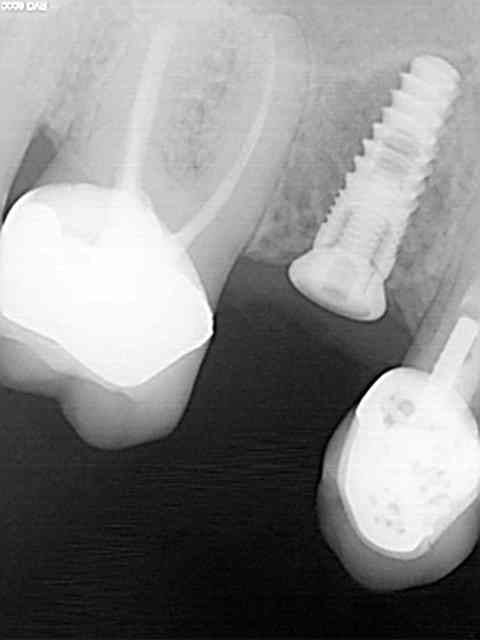

Comme promis, je donne des nouvelles de mes débuts avec le Legacy 3.

1er implant avec ce système, ce matin.

Remplacement, d'une 15 fracturée. Dent extraite en décembre 2011, attente de la cicatrisation à cause de l'infection importante autour de la dent et pose aujourd'hui d'un 3.7 longueur 10.

Quelques radios pour illustrer le cas...

Js 1 wjplje - Eugenol

Js 2 vpryz9 - Eugenol

Js 3 orny9q - Eugenol